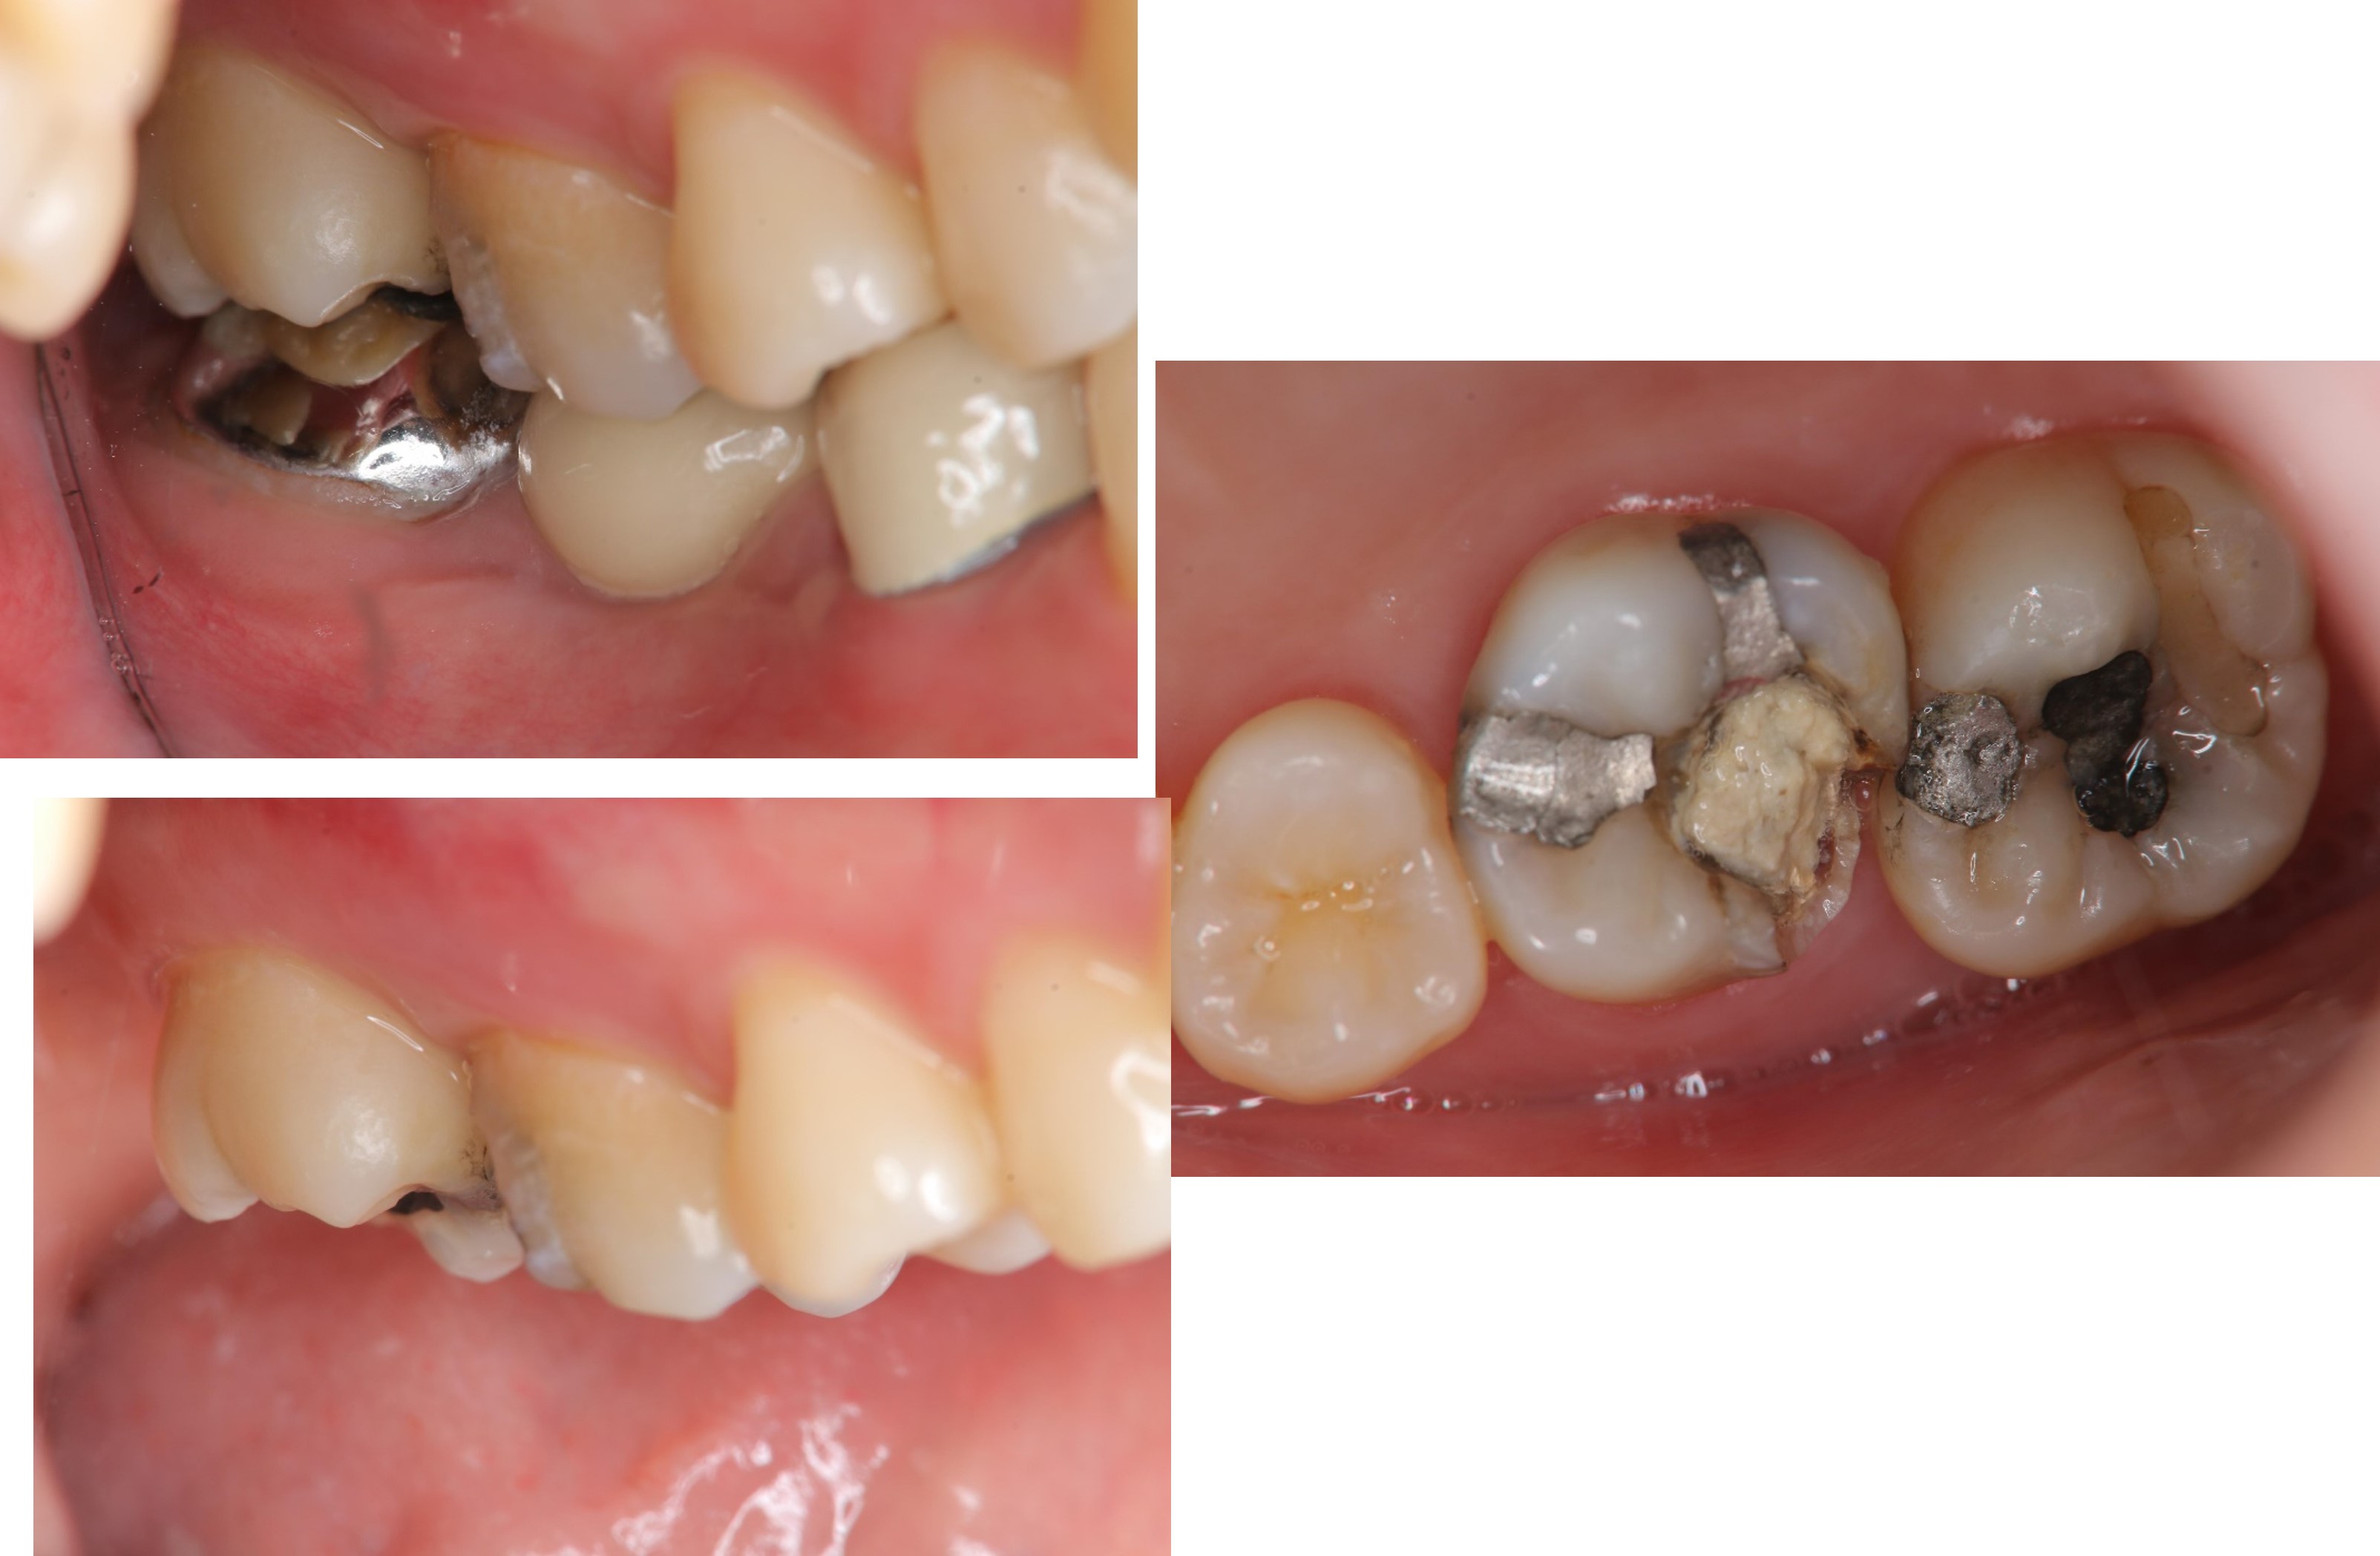

治療前,右上第一大臼齒疼痛

治療前,第一大臼齒蛀牙